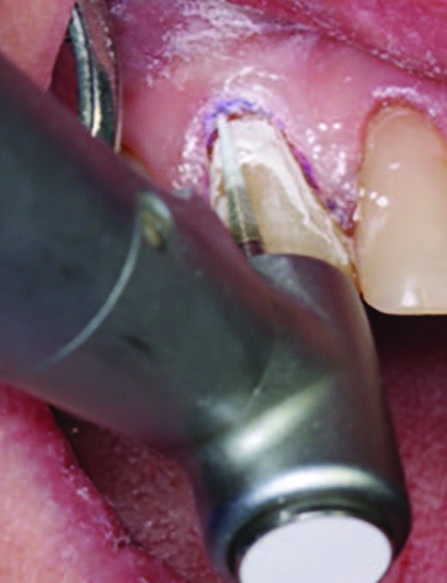

Figure 1.

Initial presentation of tooth #6 showing the Class V lesion with dislodged previous restoration and exposed dentin.